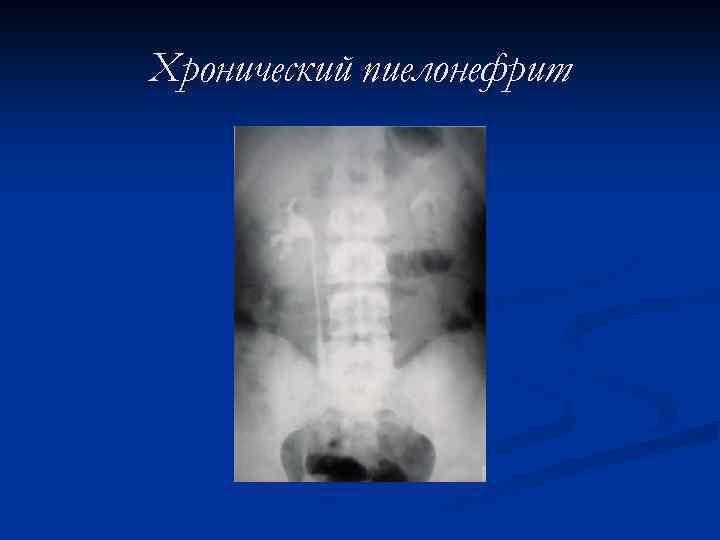

Хронический пиелонефрит